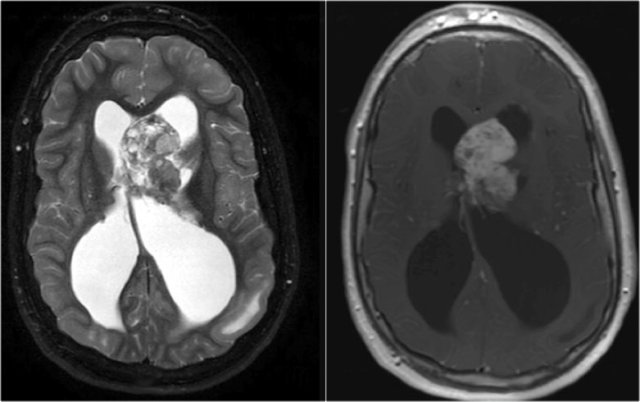

T2WI and T2* gradient echo show multiple cavernomas.

Notice the popcorn appearance with peripheral rim of hemosiderin on the T2WI.

The lesions are almost completely black on the gradient echo due to blooming artefacts.

T2* and susceptibility weighted imaging (SWI) markedly increase the sensitivity of MRI to detect small cavernomas.

The five black dots in the left cerebral hemisphere on the T2* are also cavernomas and are not visible on the T2WI.

Axial T2WI and T1WI-CE show a giant cell astrocytoma at the level of the left foramen of Monro causing obstructive hydrocephalus.

Also notice tuber on the left.